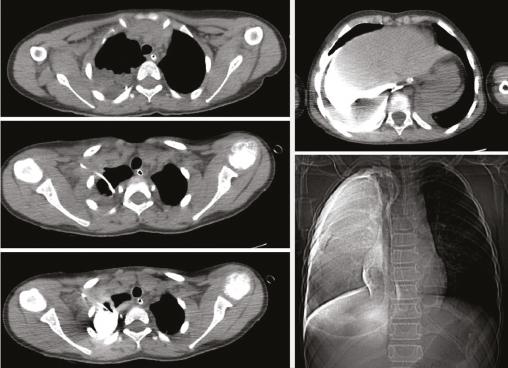

La tomodensitométrie montrait un épanchement pleural droit de moyenne abondance avec collapsus pulmonaire passif en regard, des lacérations hépatiques et une fracture rénale. Après injection de produit de contraste iodé, on notait un remplissage de l’espace pleural droit sans aucune opacification vasculaire secondaire à une position intrapleurale de la voie veineuse centrale (v. figure ). Une hydratation avec surveillance rapprochée des constantes de l’enfant ont été préconisées, l’évolution a été simple, sans complications immédiates ou tardives.

La tomodensitométrie montrait un épanchement pleural droit de moyenne abondance avec collapsus pulmonaire passif en regard, des lacérations hépatiques et une fracture rénale. Après injection de produit de contraste iodé, on notait un remplissage de l’espace pleural droit sans aucune opacification vasculaire secondaire à une position intrapleurale de la voie veineuse centrale (